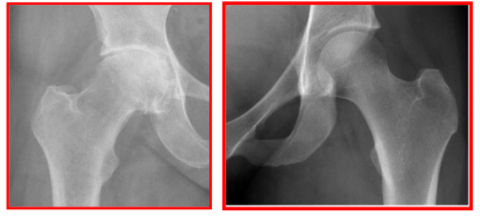

Vilka röntgenfynd är typiska vid artros?

Sänkt ledspringa → Ledspringan är avståndet mellan benen i en led. Normalt håller brosket jämt avstånd men vid artros försvinner brosket och springan minskar. Detta är det tydligaste tecknet på artros.

Osteofyter (benpålagringar) → ostefyter är små benknölar eller utskott som bildas längs ledkanterna. De bildas för att stabilisera en skadad led. Syns som utväxter längs ledens kanter.

Subkondral skleros → Förtjockning och förhårdning av benet precis under brosket (subkondralt ben). Syns som ljusare, tätare område på röntgen. När brosket inte längre dämpar stötar → mer kraft överförs direkt till benet vilket gör benet tätare och hårdare.

Subkondrala cystor → små hålrum i benet fyllda med vätska. Uppstår pga ökat tryck i leden så synoviqalvätska pressas in i benet eller mikroskopiska fraktirer.